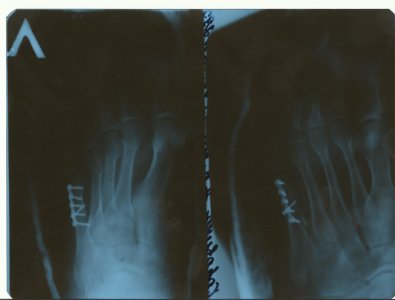

Многооскольчатый открытый внутрисуставной перелом дистальной трети правого бедра и проксимальной трети обеих костей правой голени со смещением отломков, разможжение мягких тканей в области правого коленного сустава(IО-3-4 gj Muller)Закрытый перелом таранной кости правой стопы со смещением отломков.Осл. постравматическая анемия, невропатия нервных стволов голени, посттравматическая аклюзия правой передней б/берцовой артерии. Жду ответа с нетерпением.

Конкретно ответить не могу, не видя ребенка, но так быывает. Возможно само пройдет. К врачу.У сына (13 лет) был перелом 3 и 4 плюсневых костей без смещения. На 24 дня наложили лангету, которую сняли 2 дня назад. Сейчас не наступает на пятку, говорит, что очень больно, и костыль не бросает. А сегодня поскользнулся и сильно наступил на всю стопу, после этого нога болит и в состоянии покоя. В области перелома боли нет. Врач из процедур рекомендовал только ванночки с морской солью. Подскажите является ли это обычной реакцией после снятия гипса и что можно порекомендовать в данном конкретном случае.